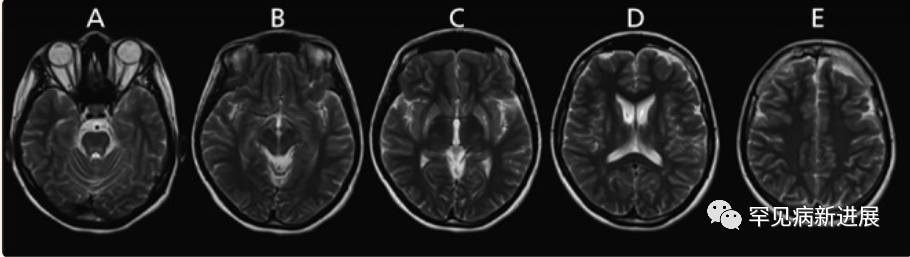

威尔逊病(Wilson disease,WD)是一种罕见的遗传病,会导致铜在肝脏、大脑、角膜、肾脏和心肌中病理性沉积。本文介绍两例伴有进行性运动障碍的神经系统WD,检查 Kayser-Fleischer 环(K-F环)阳性,转氨酶正常,血清铜和铜蓝蛋白低和 24h尿铜增加。颅脑成像显示 T2/FLAIR 对称性基底节高信号。由于其罕见性和表现形式多样,这些病例常被忽视和误诊。需要多种检查明确诊断,且越早干预,预后越好。

病例情况 病例一:伴有帕金森症状的共济失调型;病例二:伴有帕金森症状的肌张力障碍。两名患者均接受裂隙灯检查有 K-F 环(图1)。 肝脏超声检查有明显结构异常,实验室检查肝功能正常,低血清铜、低铜蓝蛋白和尿铜排泄增加,均无基因检测。(表一) 据统计50% 的肝脏和 99% 的神经系统病变患者有K-F 环(后弹力膜上铜沉积)。 表2: 第8届WD国际会议诊断标准(Leipzig评分) 注:总分≥4分可确诊;总分3分为疑似诊断,需进一步检查;总分≤2分基本不考虑诊断;a:肝铜定量不可及时;ULN:正常值上限 脑部磁共振成像未显示典型的双熊猫征,但在壳核、尾状核和丘脑核上显示对称的 T2/FLAIR 高信号(图 2和图 3)。 两案例均高度暗示了矿物沉积,根据 Leipzig评分,均是 WD 的明确案例。 案例 1 的T2加权序列的代表性图像。背侧区域有高信号B.上中脑轴向切开;中脑被盖上有汇合的高信号C.外侧裂轴向切开;外侧丘脑、尾状核和壳核区有明显的高信号D.岛状区轴向切开;在丘脑和基底神经节可见广泛的双侧高信号E. Corona radiata 轴向切割;双侧半卵圆形未出现任何信号异常 案例 2 的T2加权序列的代表性图像。脑桥背侧区域有高信号B.上中脑轴向切开;黑质C区有外观正常的红色核高信号。壳核上有明显的高信号,有磁化率伪影区域,左侧多于右侧D.侧脑室区域轴向切割,壳核和尾状核上可见连续广泛的高信号E.冠状放射状轴向切割,双侧半卵圆形未见任何信号异常。 由于这种疾病的罕见性,启动基于人群的筛查并不具有成本效益。但对于无法解释的神经系统疾病伴或不伴相关肝病的患者,筛查应该强制性。WD 须与诸如特发性震颤、年轻发病的帕金森病、全身性肌张力障碍和其他罕见的运动障碍(如亨廷顿病、Hallervorden-Spatz 病、特发性扭转性肌张力障碍、舞蹈病-棘红细胞增多症和良性家族性舞蹈病)区分开来。因此,WD 是一种诊断紧急情况,需要立即全面检查。 管理 至于治疗,明确的治疗包括肝移植,特别是对于急性肝炎或暴发性肝功能衰竭的患者。对严重和神经系统后遗症患者,最好的选择是直接增加尿中铜的排泄,即 D-青霉胺和曲恩汀,或阻断胃肠道对铜的吸收,即锌剂和四硫代钼酸盐(表三)。低铜饮食是主要的治疗方法,并补充锌,随后注意到言语、震颤和四肢僵硬的显著改善。第一个病例接受了 D-青霉胺治疗,药物输注缓慢以减少血液不良后果并监测反常的神经功能恶化。至于第二个病例,由于基线神经系统状态相对严重且恶化风险高,该患者继续服用锌补充剂。因无两个相同 WD 患者,治疗应个体化。对螯合剂和药物治疗无效的衰弱性运动障碍患者,可提供肉毒杆菌毒素注射。筛查患者的兄弟姐妹并监测他们的血清铜蓝蛋白也是管理的重要组成部分。早期干预有更好预后,治疗应紧迫。 表三